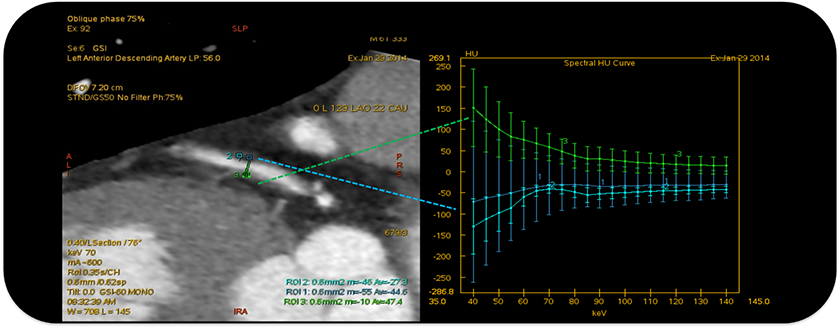

轴位图示:典型的“餐巾纸环”征,预示该斑块为含脂质核心的易损斑块 能谱曲线图示:更低密度区呈现反向曲线(红色)与置于心包脂肪间隙的能谱曲线(绿色)相一致;与其余软斑块区的能谱曲线(蓝色,正向)不同, 提示为含脂质成分

2条蓝色曲线:斑块含脂性成分, 1条绿色曲线:纤维斑块